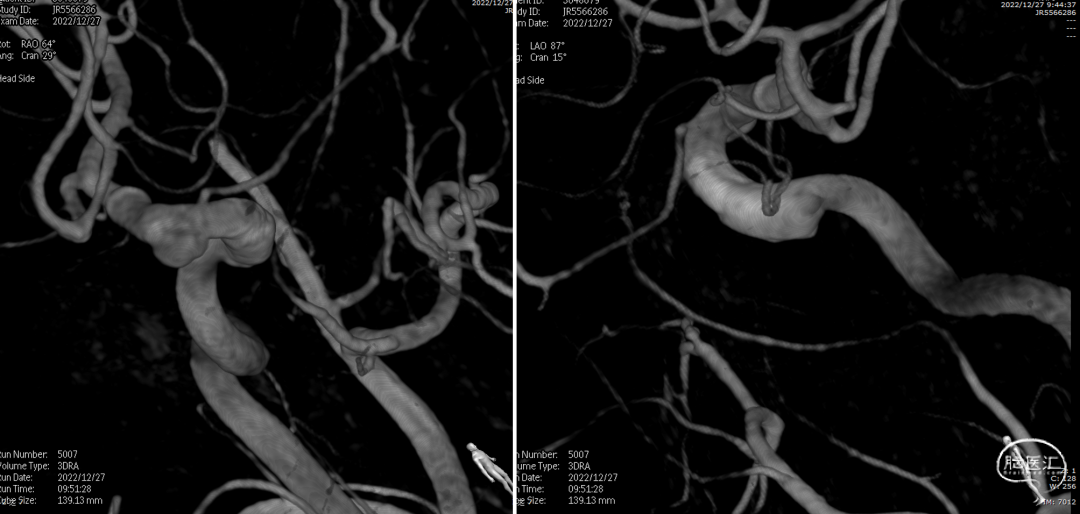

术后复查右颈内动脉造影(2022-12-27)

术后复查右颈内动脉3D重建

复查左颈内动脉造影(2022-12-27)

术后3D重建

术后3D图像及透视

术前、术后3D图像对比